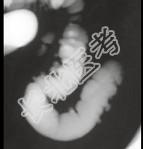

- 单项选择题男,52岁, 习惯性便秘2年余,结合图像, 应诊断为 ( )

A、溃疡性结肠炎

B、结肠憩室病

C、假膜性结肠炎

D、结肠息肉病

E、结肠转移瘤